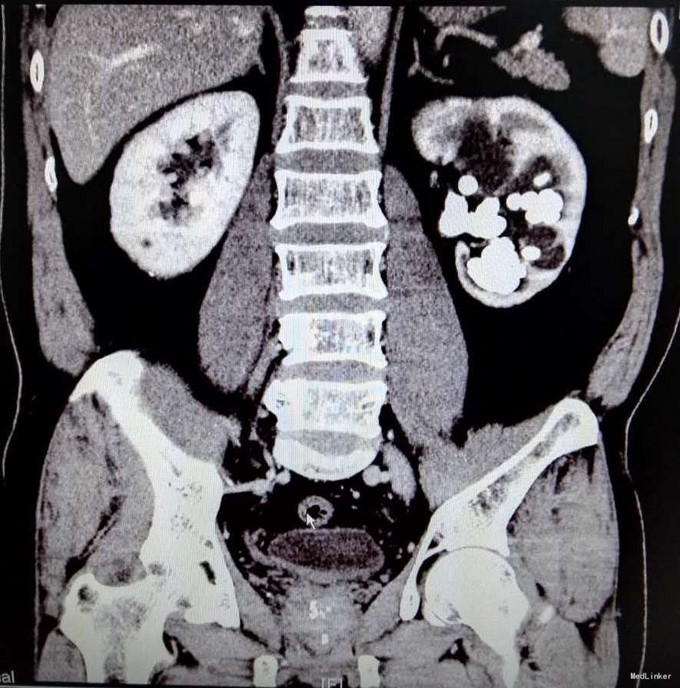

3、查体:未见明显阳性体征 4、辅助检查:外院平片:双肾多发结石;我院CTU:双肾多发结石,左侧肾盂输尿管连接处结石,并双肾积水,左肾明显,双侧肾盂、输尿管炎症。

5、诊断:肾结石(双肾多发结石) 6、治疗:入院后完善相关检查,双肾CTU:双肾多发结石,左侧肾盂输尿管连接处结石,并双肾积水,左肾明显,双侧肾盂、输尿管炎症。排除手术禁忌症后行左侧PCNL术,术后恢复良好,拔出肾造瘘管后,先出院休息,2周后返院进一步治疗